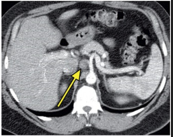

CT Scan

CT scans showed thickening of the distal esophagus.

an enlarged lymph node in the region of the gastrohepatic ligament, extending to the celiac axis.